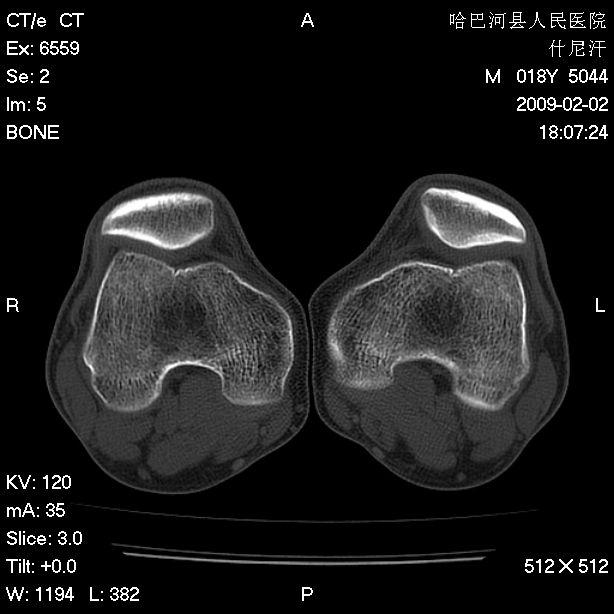

标题: CT17889:外伤后右膝关节反复疼痛3年余 [打印本页]

标题: CT17889:外伤后右膝关节反复疼痛3年余

大致正常,必要时mr检查

ct未见明显异常。关节腔未见明显积液,半月板未见明显撕裂。但最好还是mri看看韧带及半月板情况。